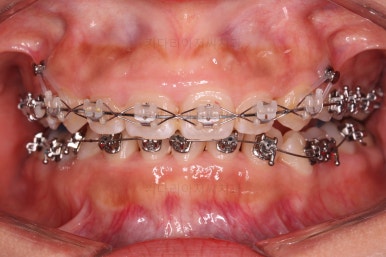

장치 부착 직후의 모습입니다.

웃을 때도 주로 윗니만 보이기 때문에 아랫니는 메탈로 해도 큰 문제 없어보이네요.

과개교합은 거의 개선이 되었고요.

위아래 치열의 중앙이 서서히 맞아지는 느낌이 드시나요?

조금만 더 하면 되겠네요.

중앙선을 맞추고 교합도 잘 맞추고 마무리를 합니다.